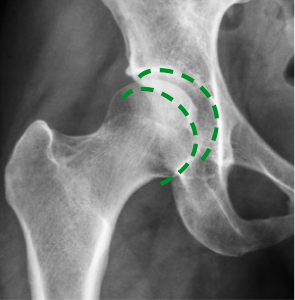

Na slici lijevo (snimljenoj prije tretmana) vidljiv je nedostatak sinovijalne tekućine, što uzrokuje trošenje kostiju. Na slici desno, zahvaljujući tretmanu, kosti se kreću glatko i bezbolno. Struktura sinovijalne tekućine se obnovila – vratila je svoja svojstva podmazivanja.

Prof. Zygler je dokazao (što potvrđuju rendgenske i ultrazvučne snimke) da njegova formula protiv artritisa potiče obnovu zglobova na tri ključna načina:

Već nakon 4-5 tjedana Zyglerovog tretmana, zglobna hrskavica će se iz tanke i ispucane pretvoriti u debelu i elastičnu. Zahvaljujući tome, smanjit će se trenje u zglobovima, a svaki pokret ćete izvoditi sigurno i s lakoćom.